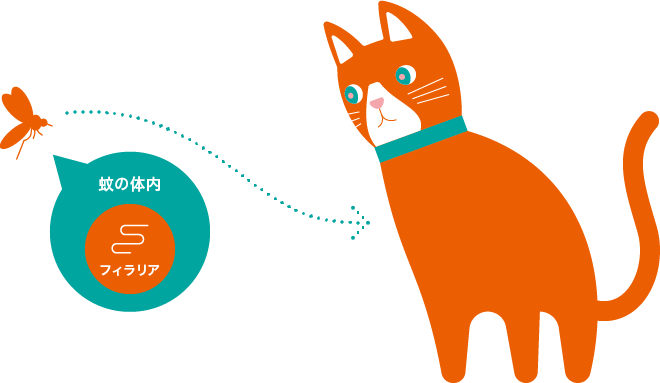

ねこのフィラリア症は、フィラリアと呼ばれる寄生虫が蚊を経由し、ねこの肺動脈や心臓に感染する病気です。

主にフィラリア感染犬の血液を吸った蚊がねこの血液を吸ったときに、フィラリアの幼虫がねこの体内に侵入し、感染します。